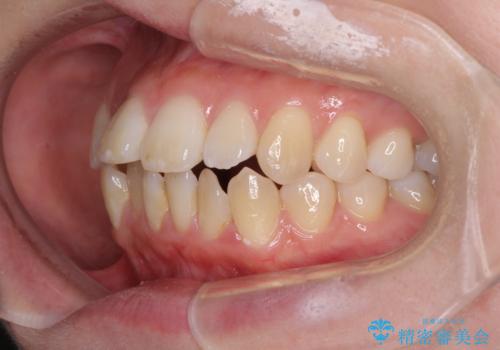

- 口元の突出感と口の閉じにくさを気にして来院された患者様です。

上下左右第一小臼歯4本を抜歯し、ワイヤー装置にて口元を引っ込めるよう矯正治療を行うこととしました。

2年~2年半が治療期間の目安でしたが、順調に治療が進み、1年9か月で満足のいく歯列となりました。